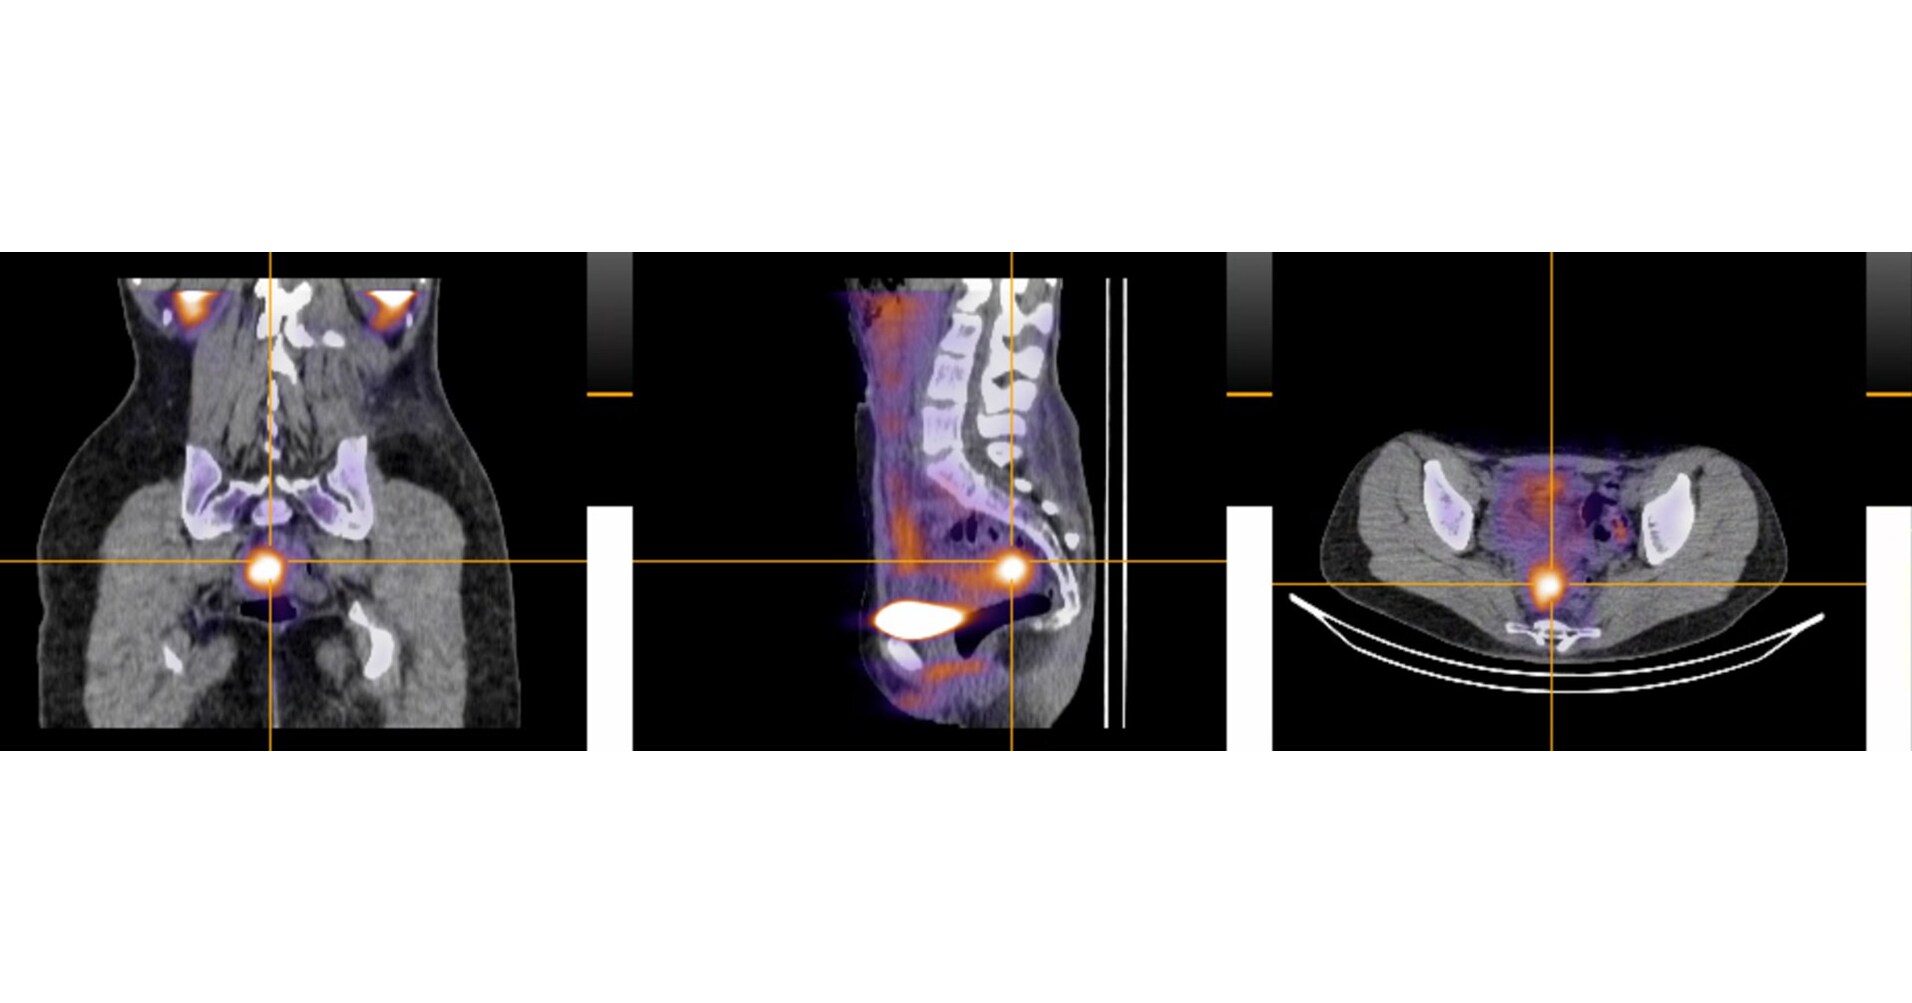

Inside 99mTc-maraciclatide: Seeing the Invisible

Unlike traditional ultrasound or MRI, which often struggle to detect small or deep-infiltrating endometriosis lesions, 99mTc-maraciclatide functions as a molecular beacon. This radiopharmaceutical binds to specific proteins overexpressed in endometriosis lesions, illuminating them on a scan with high precision.

This approach shifts the diagnostic focus from structural anatomy to biological activity. Instead of looking for a physical mass that might be too small for an MRI to capture, doctors are now looking for the chemical signature of the disease itself.